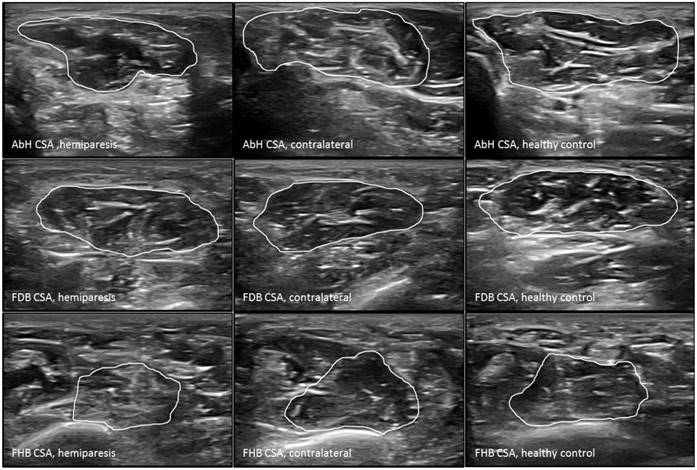

Figure 2

Ultrasound imaging measurements of the intrinsic plantar muscles CSA. Abbreviations: AbH, abductor hallucis; CSA, cross-sectional area; FDB, flexor digitorum brevis; FHB, flexor hallucis brevis.

The probe was located according to prior research studies about RUSI measures of the intrinsic plantar muscles and fascia [8-10]. First, the PF was assessed in a longitudinal line from the medial calcaneal tubercle to the 2nd toe. The PF was divided into 3 points of evaluation: 1) the calcaneus insertion (PF-1), b) the navicular tubercle (PF-2), and 3) the 2nd metatarsal head (PF-3). Second, the CSA (perpendicular to the muscle fibers) and the thickness (longitudinal to the muscle fibers) were assessed in the thickest part of the muscles (AbH, FDB and FHB) coinciding with 3 different scanning lines. Indeed, the AbH scanning line was located from the medial calcaneus bone tuberosity to the navicular bone tuberosity. After, the FDB scanning line was placed between the medial calcaneus tuberosity bone tubercle to the 3rd toe. Lastly, the FHB scanning line was longitudinally placed along the 1st metatarsal shaft (8,9). Regarding the RUSI measurements of the PF thickness (Figure 1), intrinsic plantar muscles CSA (Figure 2) and thickness (Figure 3) obtained in the hemiparesis, contralateral and healthy matched control feet, subjects who presented difficulties to evaluate the muscles and PF limits (i.e. structures larger than the probe footprint or ultrasound images with poor visually perimeters) were excluded [10].

The RUSI measurements regarding the CSA and thickness of the intrinsic plantar muscles and fascia between all groups were summarized in Table 2. Considering the intrinsic plantar muscles, statistically significant differences (P < 0.001) were only shown for the FHB thickness. The post-hoc Bonferroni´s analysis showed statistically significant differences for a FHB thickness increase of the hemiparesis feet (means difference of 0.31 cm; P < 0.001) and contralateral feet (means difference of 0.37 cm; P < 0.001) with respect to the healthy matched control feet. Regarding the fascia, statistically significant differences (P < 0.01) were only shown for the PF-2 and PF-3 thickness. The post-hoc paired Wilcoxon analysis showed statistically significant differences for a PF-2 thickness reduction of the hemiparesis feet (means difference of -0.03 cm; P = 0.006) and contralateral feet (means difference of -0.04 cm; P = 0.005) with respect to the healthy matched control feet. In addition, a PF-3 thickness reduction of the contralateral feet (means difference of -0.03 cm; P = 0.001) with respect to the healthy matched control feet. The rest of measurements did not show any statistically significant difference (P > 0.01).